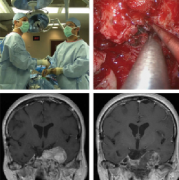

颅底肿瘤手术危险吗?

多年来,完全切除侵犯颅底中线区的肿瘤被认为是不可能的,因为这些肿籀位于各种不同的手术专科均无法处理的部位。当显露肿瘤时,显露范围狭窄,肿瘤的切除也常常是不完全的...